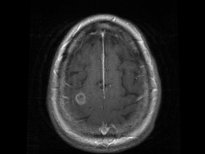

ABD'nin Washington eyaletinin Seattle kentinde yaşayan 69 yaşındaki bir kadın, su yoluyla vücuduna giren amiplerin beynini yemesi üzerine yaşamını yitirdi. Doktorlar, kadının hastalığı yüzünden sinüslerini temiz suyla yıkaması gerekirken musluk suyu kullandığı, amiplerin de musluk suyundan önce burnuna ardından kan yoluyla beynine sızdığı sonucuna vardı.

ABD'de yaşayan bir kadın, su yoluyla burnundan giren amiplerin beynini yemesi nedeniyle hayatını kaybetti.